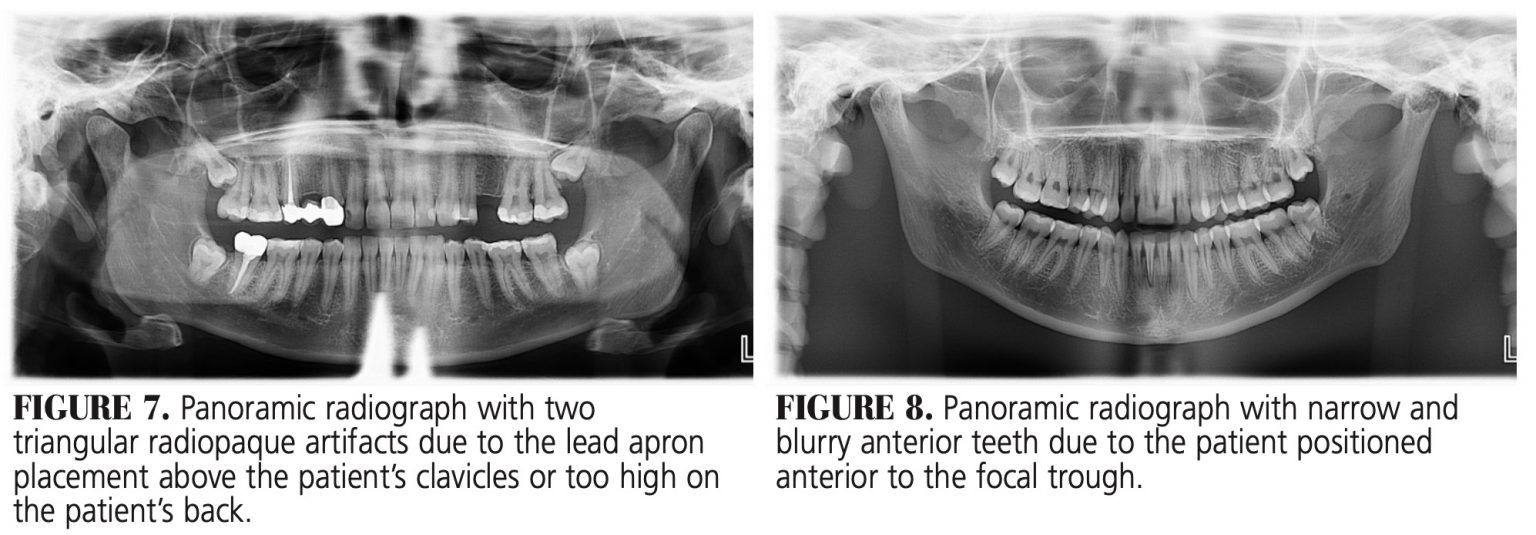

Pano Xray Errors Dentistry, Dental assistant study, Dental health care Dental Xray Errors The most common being improper exposure settings. Recognize items needing to be removed. Table 5 lists various errors that can occur with panoramic imaging. Improper time selection is the most likely error. Incorrect exposure can be caused by many factors; Learn how to avoid and correct common errors in intraoral radiography, such as placement, alignment, and angulation. It is important. Dental Xray Errors.

Extraoral panoramic errors a summary for dental assistants DentistryIQ Dental Xray Errors Are you or your team doing any of these, and if so, what can you do to correct your process? The most common being improper exposure settings. Learn how to avoid and correct common errors in intraoral radiography, such as placement, alignment, and angulation. It is important for the clinician to be able to understand errors when they occur and. Dental Xray Errors.

Reduce Your Panoramic Imaging Errors Dimensions of Dental Hygiene Dental Xray Errors Improper time selection is the most likely error. It is important for the clinician to be able to understand errors when they occur and how to correct them. Recognize items needing to be removed. The ada recently released new guidance in jada on safety and regulatory aspects of radiography, which updates portions. Are you or your team doing any of. Dental Xray Errors.